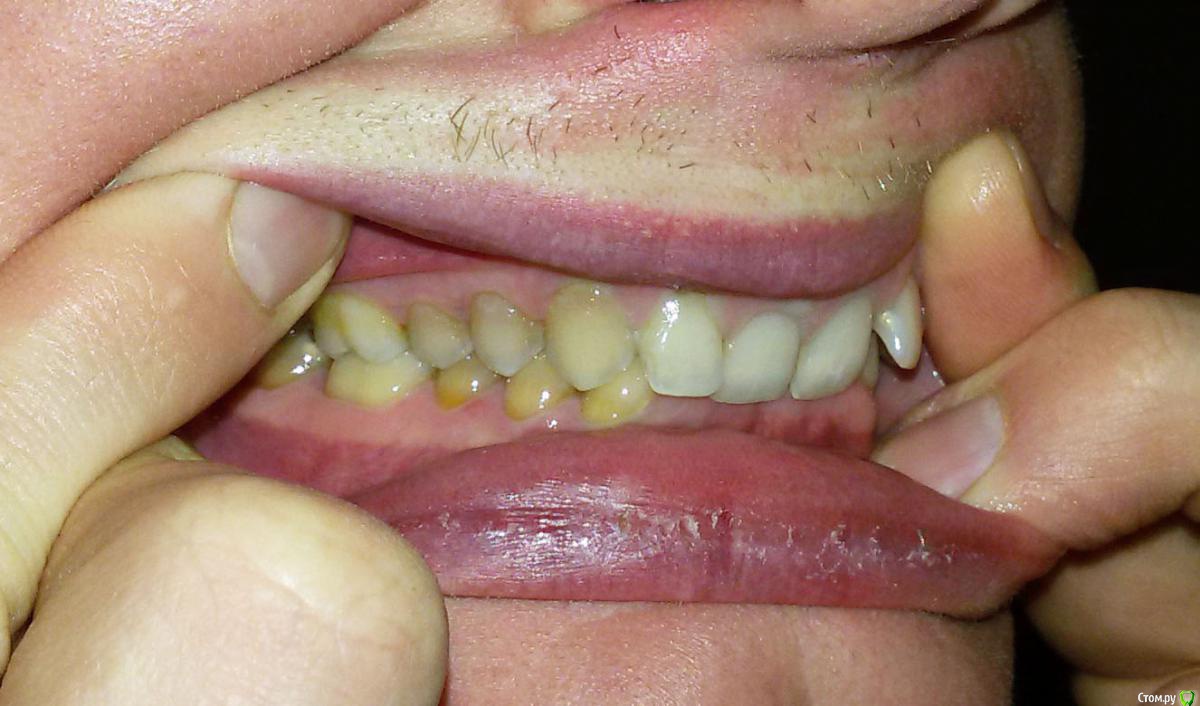

Беспокоит: Возраст 30 лет.  с 15 лет щелчки в суставе, полгода назад появилась периодическая боль - в области сустава, напряжение в жевательных мышцах, в шее  (с шеей вообще давние проблемы - не знаю, что первопричина болей), боли в затылке, голове. Глубокий прикус. Решил прикус исправлять в надежде, что боли уменьшатся.  На снимках видно, что челюсть нижняя заблокирована в заднем положении, мешают верхние резцы, головка сустава смещена

Часть из этого прикрепляю сюда. Ниже - заключение МРТ

Частичное переднее смещение суставного диска ВНЧС справа в положении с закрытым ртом, полная репозиция диска в положении с открытым ртом. Частичное переднее смещение наружного отдела суставного диска ВНЧС слева в положении с закрытым ртом (за счёт внутренней ротации диска), полная репозиция диска в положении с открытым ртом. Остеоартроз ВНЧС справа 1 ст.